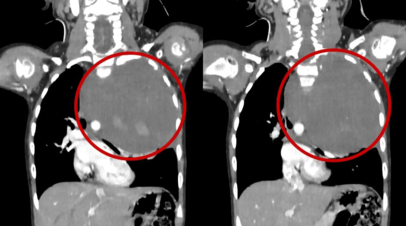

Специалисты по месту жительства выполнили компьютерную томографию, по результатам которой в грудной клетке было выявлено огромное новообразование, распространяющееся на подключичную область и шею.

После телемедицинской консультации ребёнка направили в РДКБ. Повторное обследование подтвердило наличие гигантского новообразования размером 10 на 12 сантиметров, которое занимало 75% плевральной полости.

Опухоль смещала аорту к центру грудной клетки, сдавливала левое лёгкое и сердце. Сквозь плотную ткань опухоли проходили крупные сосуды: позвоночная артерия, питающая головной мозг, и подключичная артерия с её ветвями, питающая левую руку.